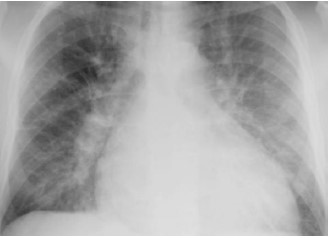

À chegada, apresenta-se sudoreico, sonolento, com vômitos. Ao exame clínico: PA 76x56, FC 118, FR 26, SatO2 85% a.a., TEC 4s. Propedêutica cardíaca: presença de B3 e de estase jugular a 45º. Propedêutica pulmonar: presença de estertores finos bibasais à ausculta respiratória.

Exames complementares: Glicemia 330 mg/dL, Na 137mEq/L, K 3,5mEq/L, Cl 101 mEq/L, troponina I 2,35mcg/L (VN < 0,014mcg/L), gasometria arterial com pH 7,15, PaO2 57mmHg, PaCO2 28mmHg, bicarbonato 10mEq/L, BE -14.

Segue radiografia de tórax.

Para esse paciente, assinale a opção que apresenta o tipo de acidente e o distúrbio gasométrico.